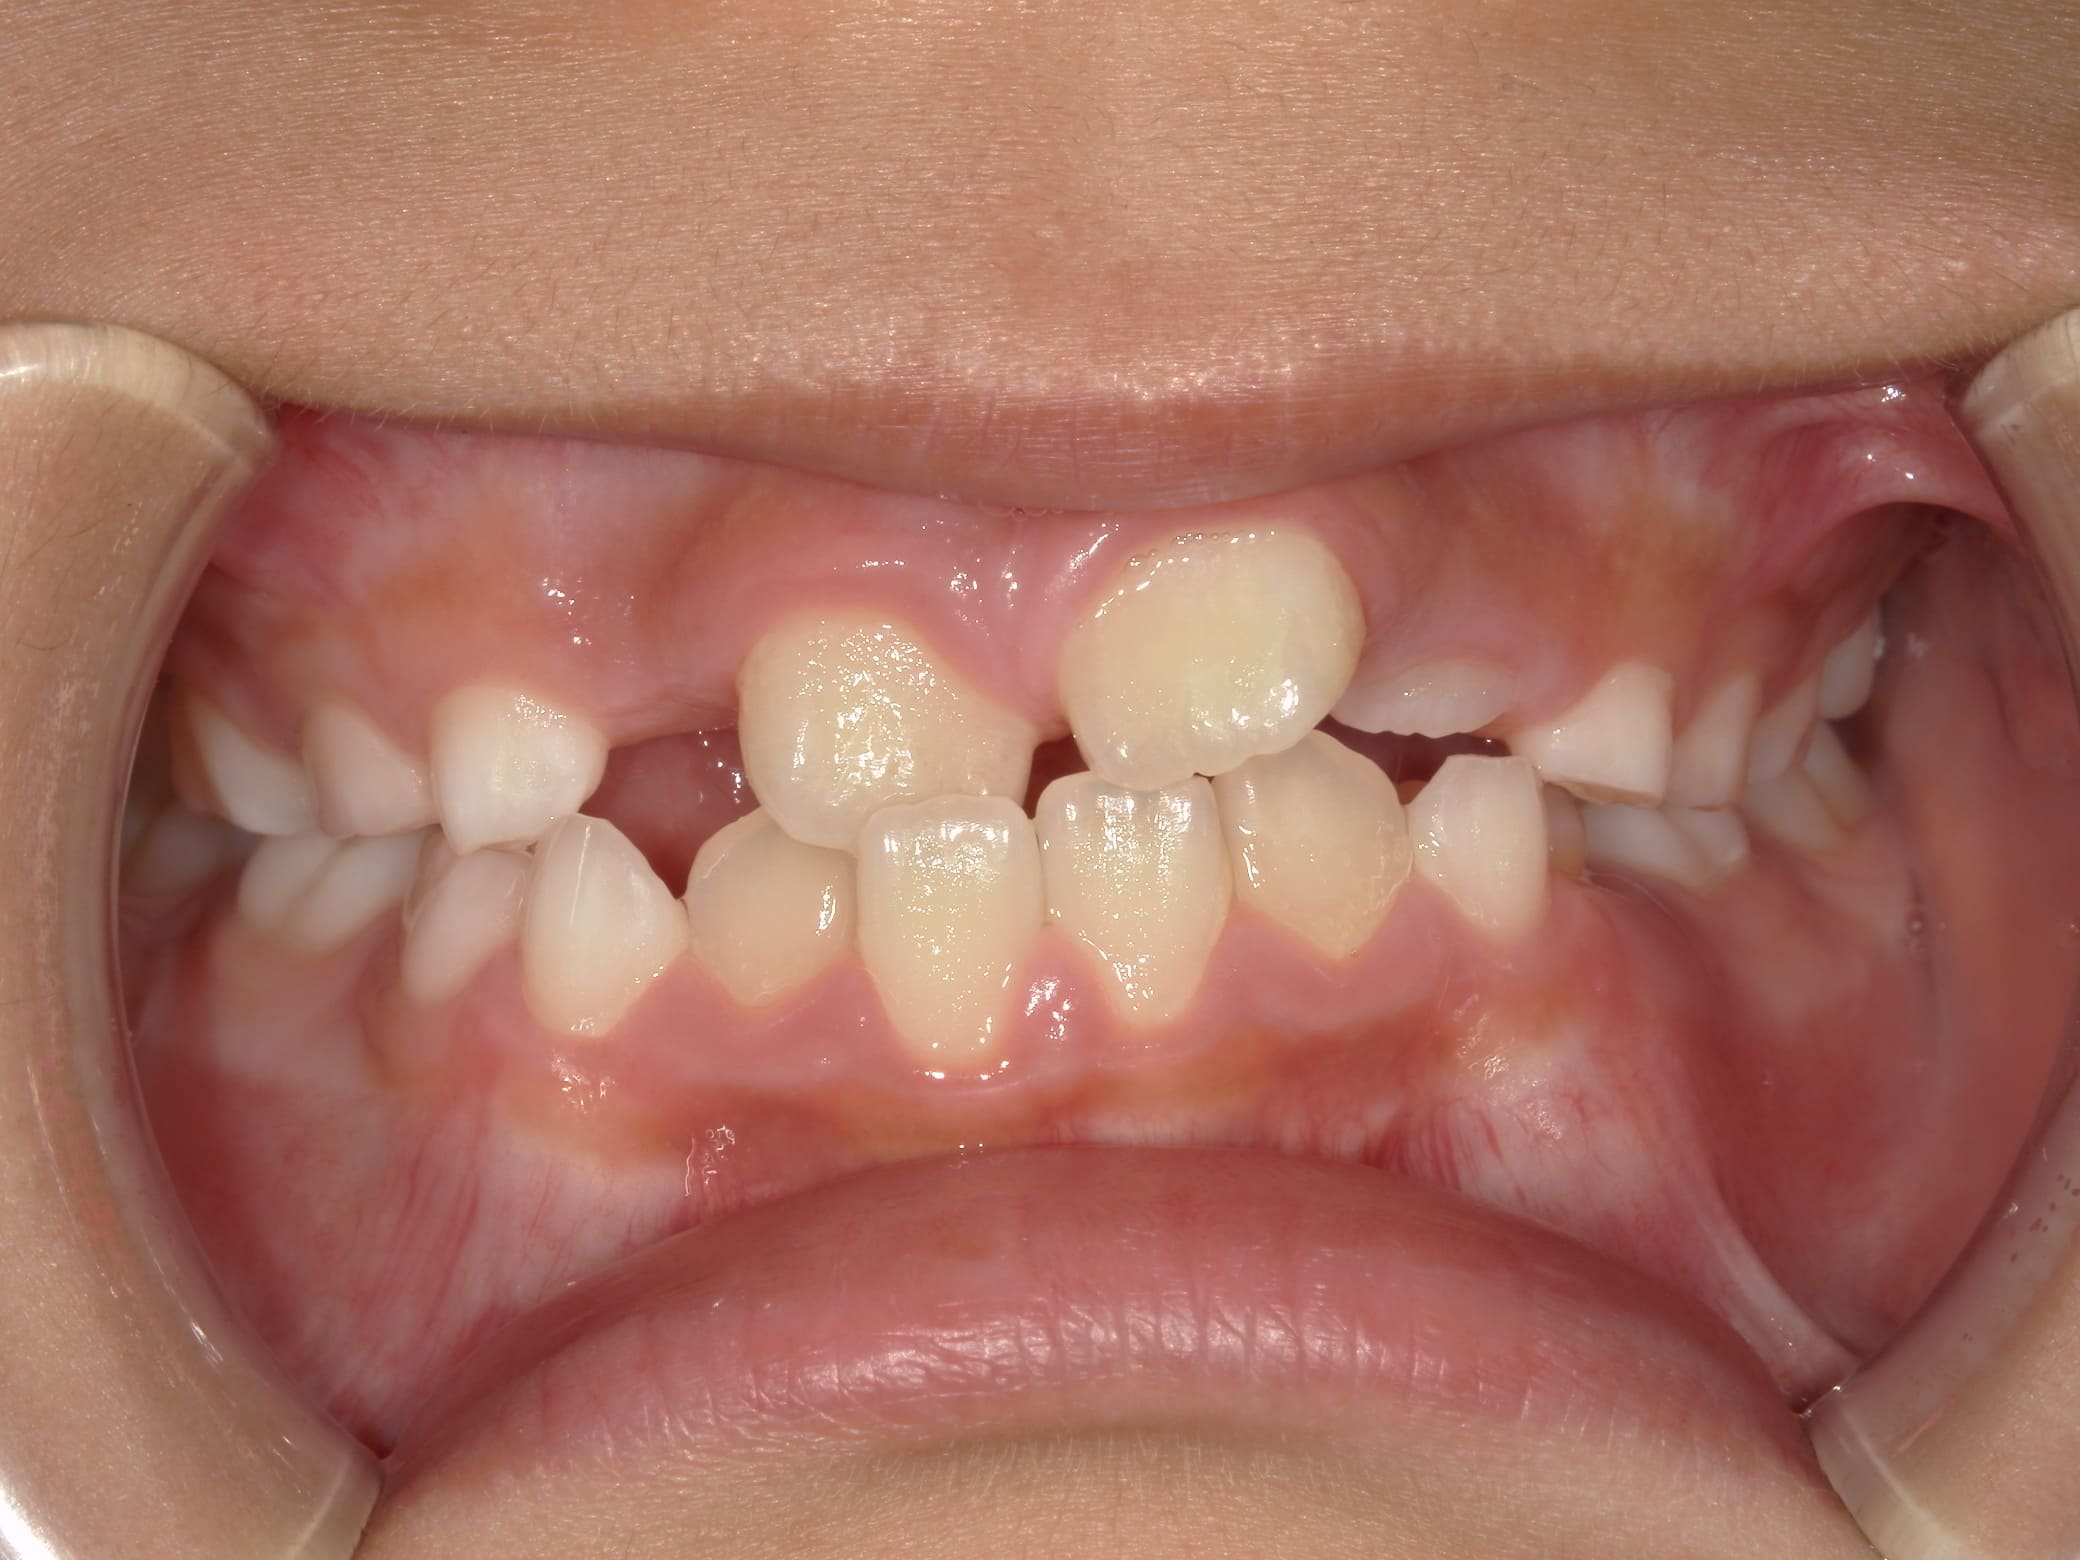

| 年齢・性別 | 7歳1ヶ月の男児 |

|---|---|

| 主訴 | 歯の生えるスペース不足が懸念され、歯列の乱れ(叢生)を整えるために来院された患者様です。 |

| 治療期間・回数 | 1年3ヶ月・11回 |

| 費用 | 420,000円(税別) |